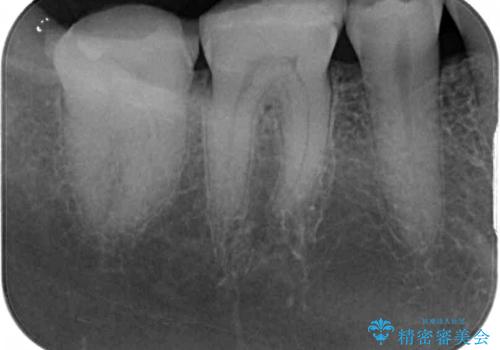

- 以前、職場近くで夜遅くまで治療していた医院で装着した奥歯のクラウンが、壊れたり汚れたりしていることを気にして来院された患者様です。

以前は安価であったことからハイブリッドクラウンを選択されたそうですが、すぐに具合が悪くなってしまったので、今回はオールセラミッククラウンにて補綴治療を行うこととしました。

咬合力が強く、土台の歯の高さが低かったたため、より高強度のフルジルコニアクラウンにて補綴治療を行いました。